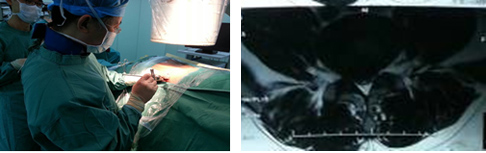

患者是一名19岁青年,因右下肢放射痛入院,疼痛的范围为大腿及小腿后外侧,入院前曾接受多方治疗,牵引、药物及其他理疗均未见效,疾病严重影响其生活及工作,基本只能卧床休息。MRI检查示L4/5椎间盘右侧巨大突出,压迫神经。对这类患者,手术指征明确,传统手术方式为腰椎后路L4/5开窗髓核摘除术,手术创伤大,术中需要剥离后方肌肉,手术时间长,出血量大,术后恢复慢而且有可能遗留腰痛症状。对于这样年轻的患者,可能会对其今后的生活造成一定的影响。经过充分的术前准备,陈钢主任为该患者在局麻下实施了椎间孔镜下椎间盘髓核摘除,通过在椎旁13CM处C臂机监视下穿刺,定位椎间盘及椎间孔位置,放入内窥镜,在直视下将椎间盘完全摘除。由于使用局麻,患者可以在术中和主刀交流,自诉症状缓解情况,该患者术中即感觉症状明显缓解,手术结束时,患者十分高兴,因为原来不敢活动的右腿活动自如了。该患者住院两天后即步行出院。与传统手术比较,因为没有剥离肌肉及切除椎板,手术切口只有1CM,大大减轻了患者的病痛及减少了常规住院的时间。

椎间孔镜技术是真正的微创技术,并被国际脊柱外科界所承认是一种损伤最小、适应症最广的椎间盘突出/脱垂的治疗技术, 是新的脊柱外科发展趋势和重要发展方向。其采用In Side--Out Side技术,通过安全三角区进入椎间盘,摘除病变髓核后退至椎间孔外,清除脱出的碎片;中央型突出,压迫椎管超过上关节突连线的病例,采用远外侧水平入路,直接摘除突出组织;游离型、黄韧带肥厚、钙化、椎管狭窄、神经孔狭窄等病例,采用椎间孔内入路,可摘除各种病变软组织、清理骨质;可以处理所有类型的椎间盘突出,还可以处理骨质,可做椎间盘复发的微创翻修手术(对于开放手术后复发的,MED手术后复发的),配合经皮固定技术可以完成退变疾病的治疗;椎间孔镜(是整体外径仅有6.3mm的同轴内窥镜,并配备有灯光、器械工作通道、注水及冲洗通道)仅需7mm的皮肤切口,从病人身体侧方、侧后方、后方,采用水平、倾斜、垂直的入路方式,通过椎间孔直达椎间盘突出部位,在椎间盘纤维环之外做手术,不伤及椎板及黄韧带,不影响脊柱稳定性,在内窥镜直视下可以清楚的看到突出的髓核、神经根、硬膜囊和增生的骨组织,然后使用各类专用的抓钳摘除突出组织、镜下去除骨质并配合射频电极进行盘内消融、术中止血及封堵破损纤维环。创伤小:皮肤切口仅7mm(如同一个黄豆粒大小),术中出血不到 5ml,术后仅缝1针(亦可不进行缝合处理),是同类手术中对病人创伤最小、效果最好的治疗腰椎间盘突出的终极微创手术。